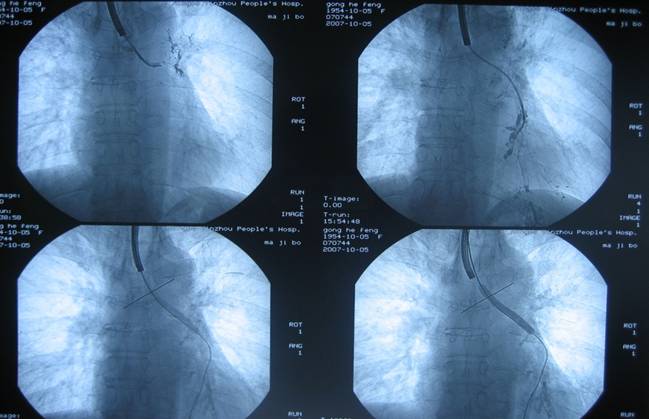

经支气管镜球囊扩张术(fiberoptic bronchoscopic balloon dilatation)

经支气管镜球囊扩张术是指在支气管镜引导下,将球囊放置于狭窄段气管或支气管,通过扩张球囊来治疗气管或支气管狭窄的方法。球囊扩张术主要用于主支气管或叶支气管狭窄的扩张治疗。

图片:

经支气管镜球囊扩张术